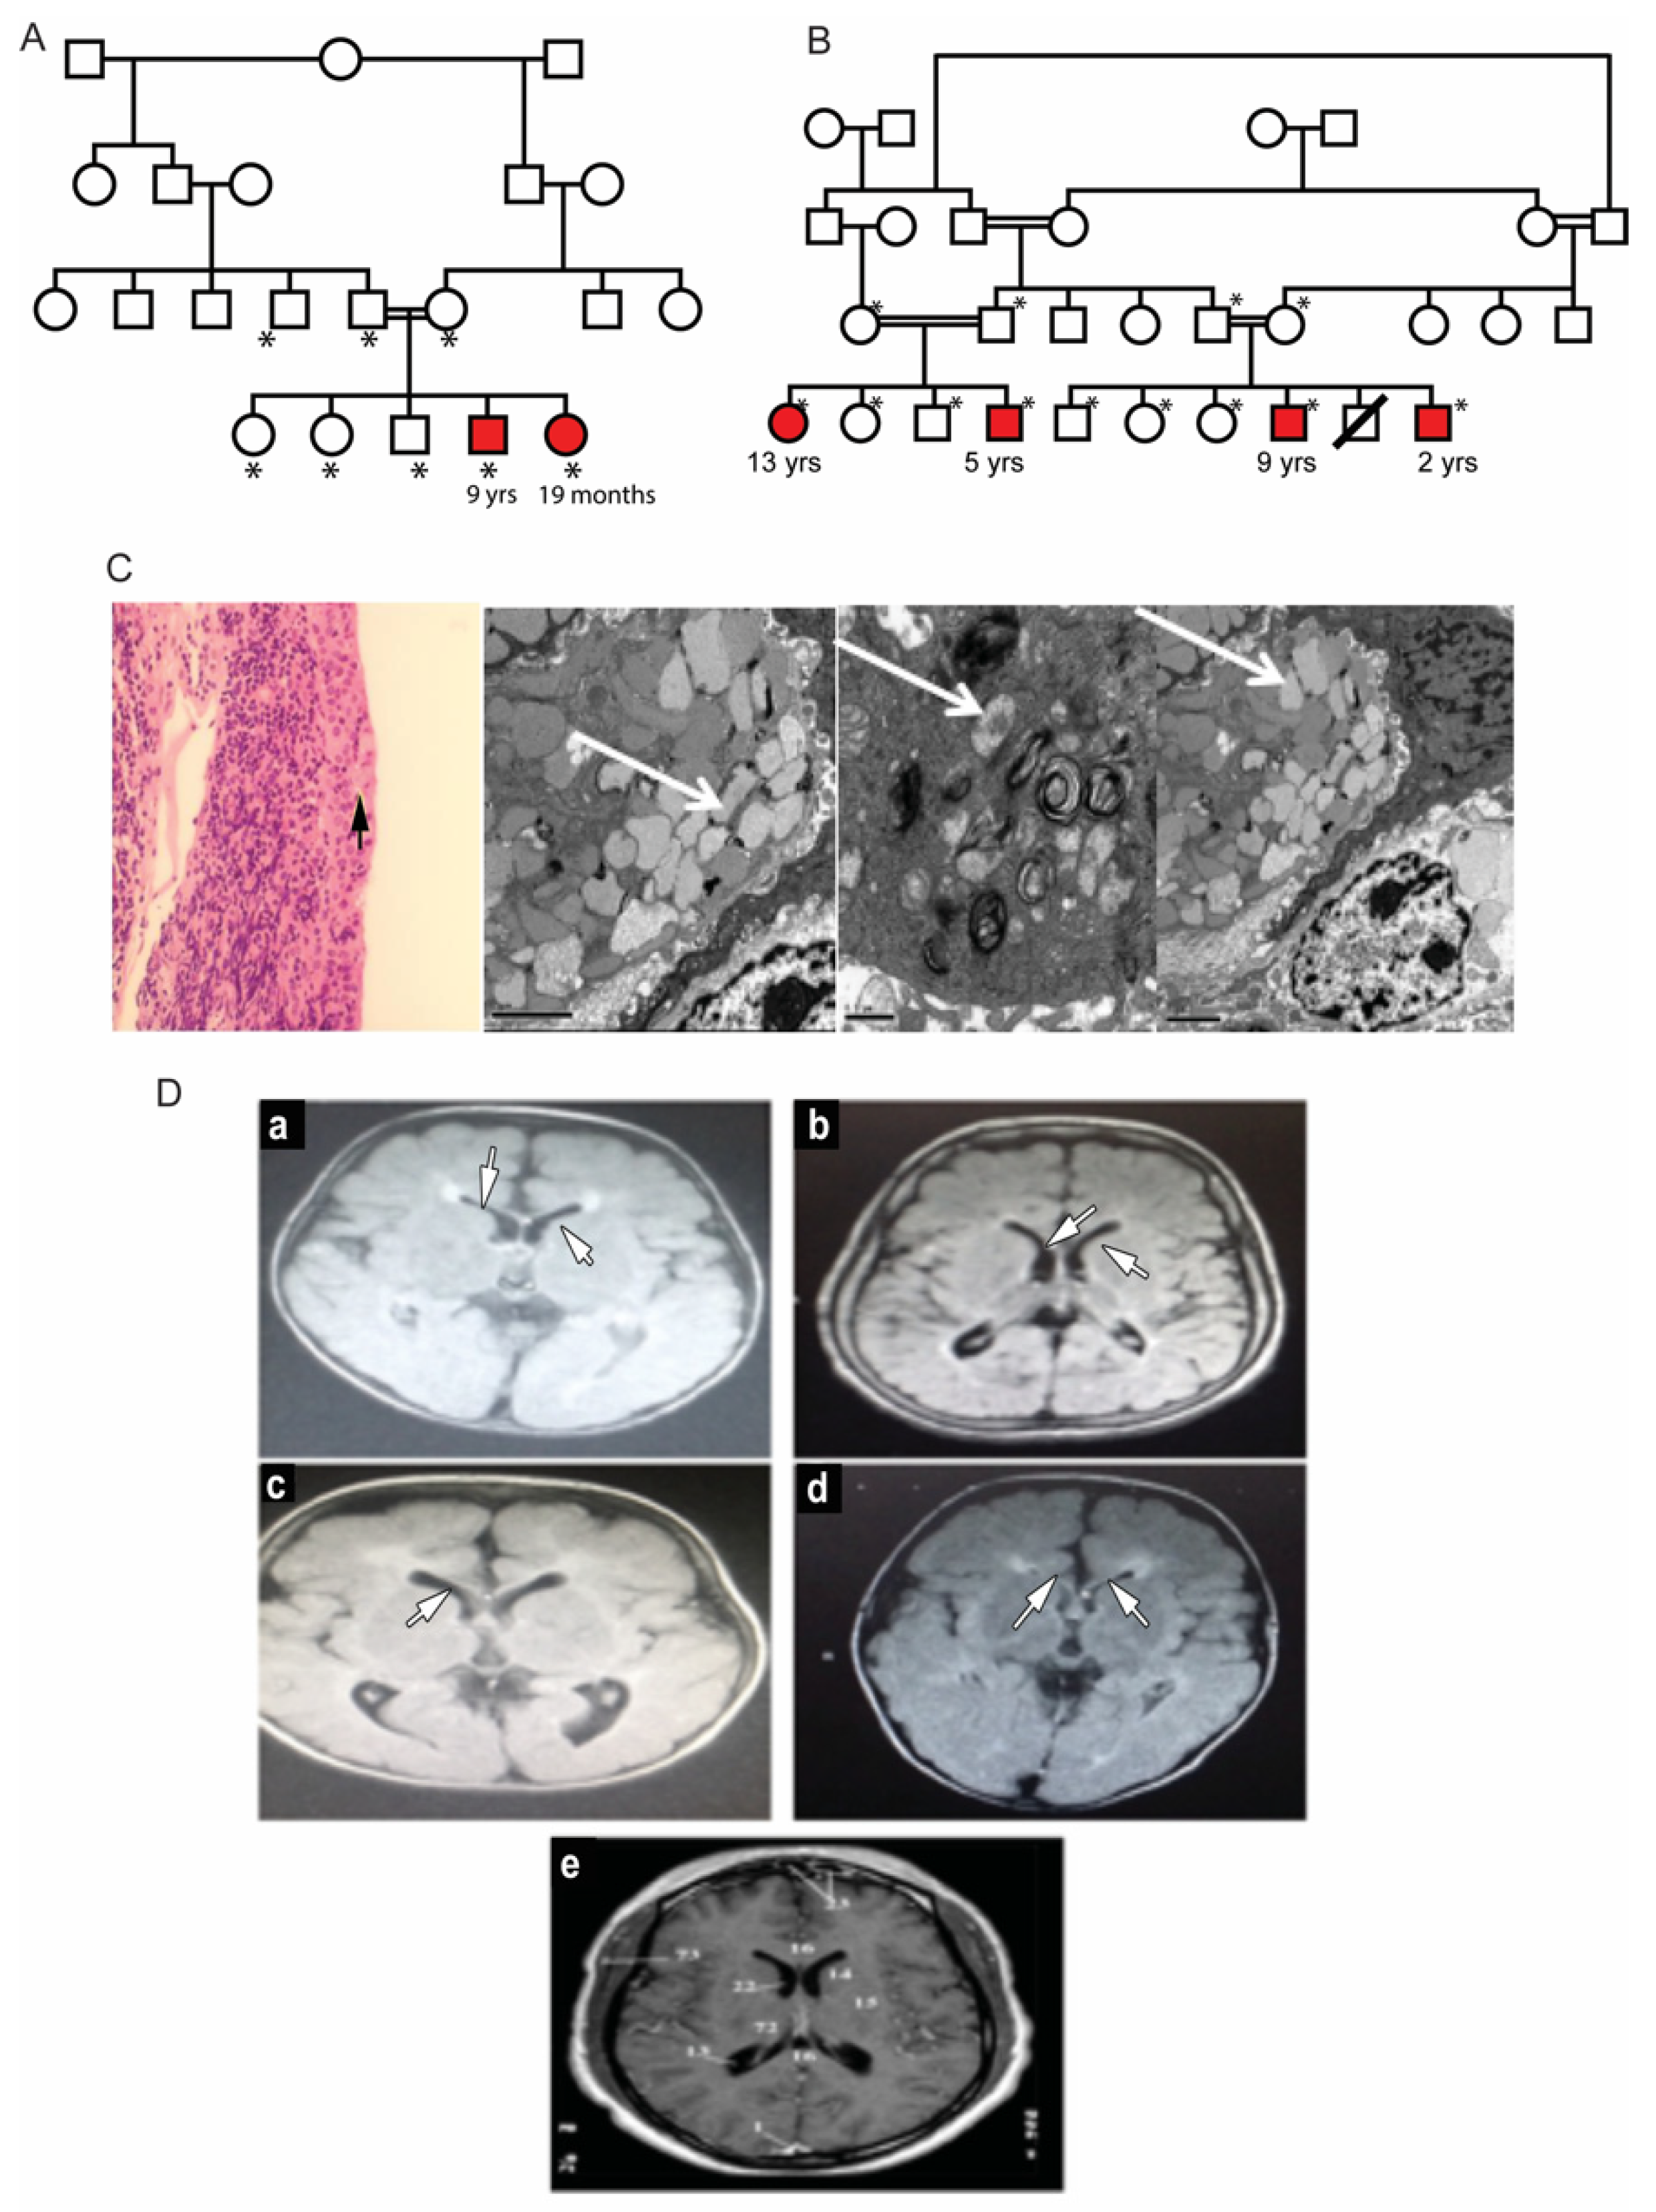

3.1. Clinical Description of Patients in Two Families

| Family 1 | Family 2 | |||||

|---|---|---|---|---|---|---|

| Patient # | 1 | 2 | 3 | 4 | 5 | 6 |

| Age | 9 yrs | 19 months | 13 yrs | 5 yrs | 9 yrs | 2 yrs |

| infantile onset of global D.D | + | + | + | + | + | + |

| Spastic quadriplegia | + | + | + | + | + | + |

| Contractures | + | − | − | − | + | + |

| Microcephaly | + | − | + | + | + | + |

| Dysmorphism | + | + | + | + | + | + |

| Blood Biochemistry: | ||||||

| Iron  (11–28 μmol/L)  | 2 | 5 | 2 | 4 | 2 | ND |

| Ferritin  (24–336 ng/mL)  | 2 | 5 | 2 | 5 | 2 | ND |

| Hemoglobin  (11–15 g/dL)  | 6.1 | 104 | 7 | 9 | 9.4 | 6.9 |

| Gastrin  (15–110 ng/L)  | 706 | 1691 | 1474 | ND | 801 | ND |

| Ophthalmological findings: | ||||||

| Photophobia | − | − | + | − | + | + |

| Nystagmus | + | + | − | − | − | − |

| Strabismus | RX | RE | AXT | RE | LX | LX |

| Corneal haziness | + | ++ | +++ | +++ | +++ | +++ (Rt) ++ (Lt)  |

| Pupil reaction to light | sluggish | sluggish | N | sluggish | N | sluggish |

| Pigmentary retinopathy | + | + | No view | + | No view | No  view  |

| ERG- rod cone dysfunction | +++ | ND | +++ | +++ | +++ | +++ |

| Brian MRI: | ||||||

| Thin corpus callosum | + | + | + | + | + | + |

| Periventricular white matter changes | + | + | + | + | + | + |